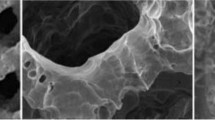

3D printed titanium also paved the way for further advancements in surface interface technology aimed at improving osseointegration and implant properties. Sheng et al. describes some of the most recent changes to functionality in titanium implants and categorized them into chemical, biologic, and physical modifications [31]. One example of a chemical modification is anodizing, whereby a current is passed through the titanium surface causing an oxidation–reduction reaction to form a surface conducive to bone healing [32, 33]. (Fig. 3a) Electrophoretic deposition (EPD) is another technique that adds a thin surface coating to titanium through an electrochemical reaction [34]. It has been used to apply inorganic coatings like hydroxyapatite, graphide oxide, and silver cations in a wide variety of orthopedic implants [34,35,36]. Physical modification includes processes that alter the internal or external structure of the implant. For example, laser surface engineering utilizes high powered lasers to melt surface material, texturizing the implant and enhancing the bone-implant interface (Fig. 3b) [37, 38]. Examples of biologic modification (Fig. 3c) include a hydrogel matrix that can absorb water and allow for controlled release of antibiotics [38], a sodium alginate gel coating containing pre-osteoblasts [39], and direct antibiotic coating. These surface modifications can be used in combination with 3D printing to enhance the efficacy and biocompatibility of spinal implants to achieve successful fusion.

Various surface modifications and resulting microstructure of a titanium implant. Microstructure is visualized on scanning electron microscopy (SEM) after a) electrophoretic deposition, b) laser peening, and c) hydrogel packing. Adapted from Sheng et al. 2022 [31]